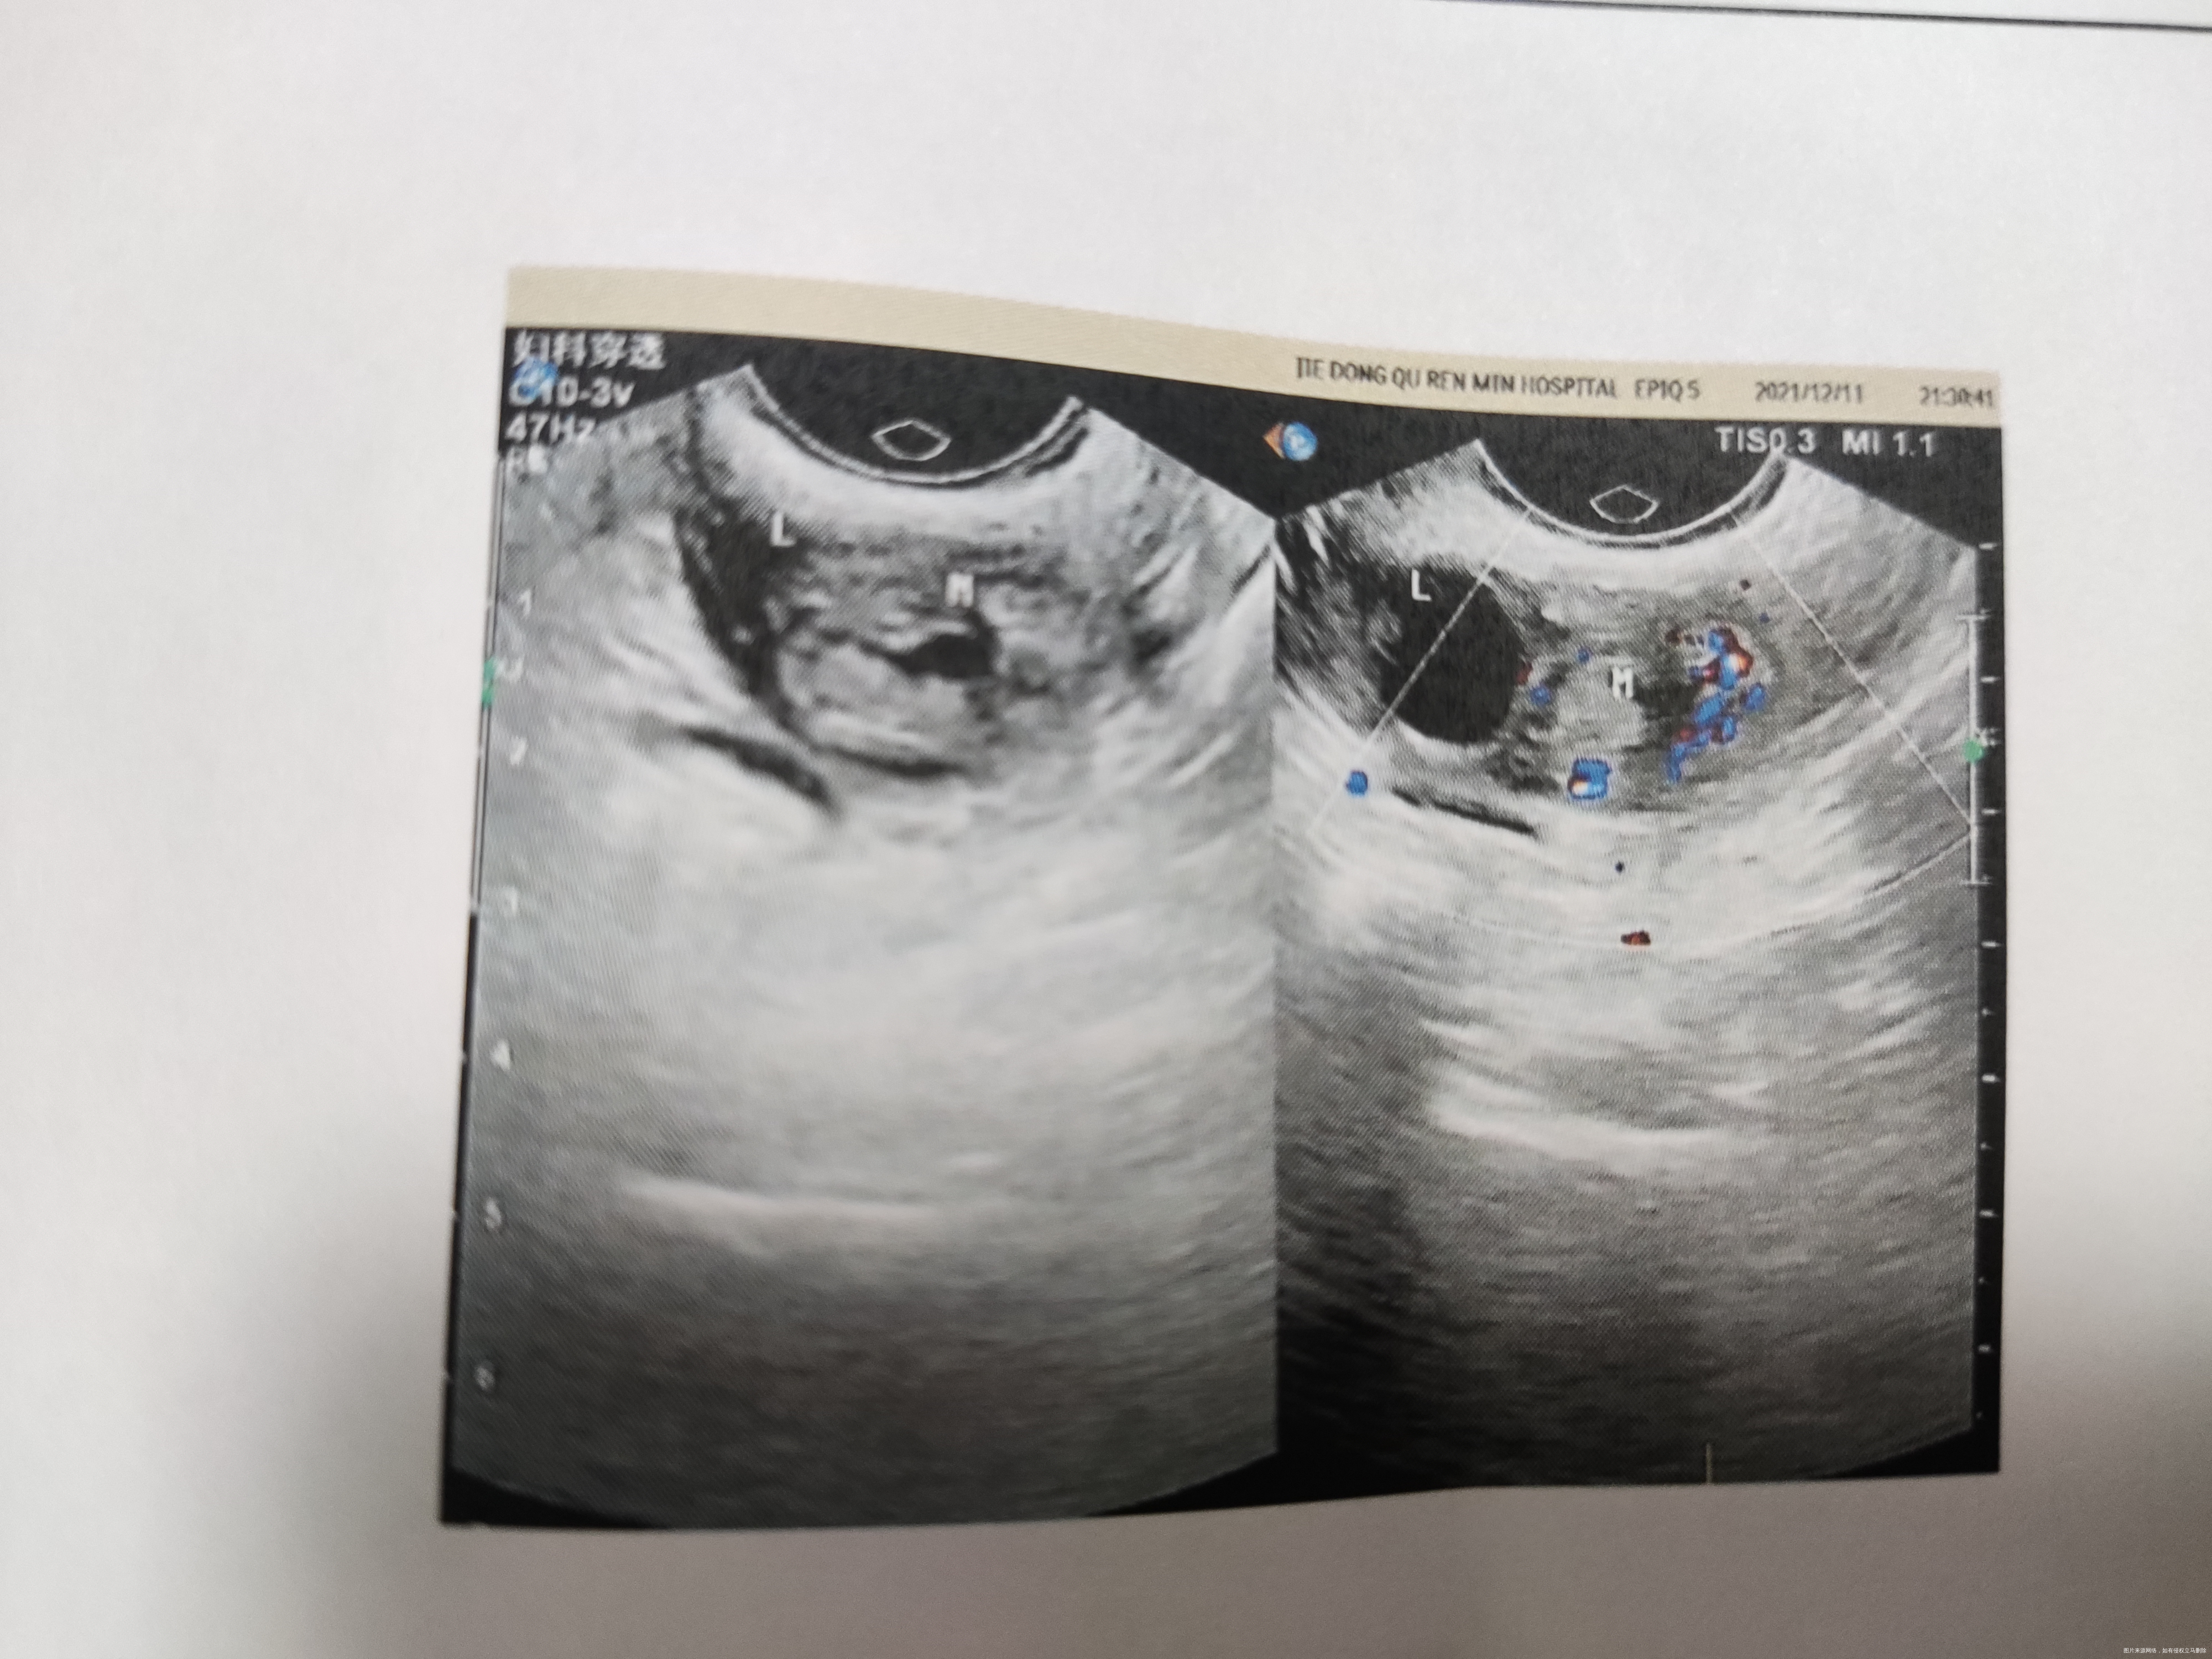

1楼hcg不高、包块不大,可以保守治疗,可能时间长,hcg下降慢。如果采用腹腔镜手术,治疗效果好,治疗速度快。

2楼目前HCG不高,盆腔和腹腔没有出血,生命体征平稳,可以保守治疗,保守治疗过程中出现盆腹腔出血,腹痛严重就要腹腔镜手术。